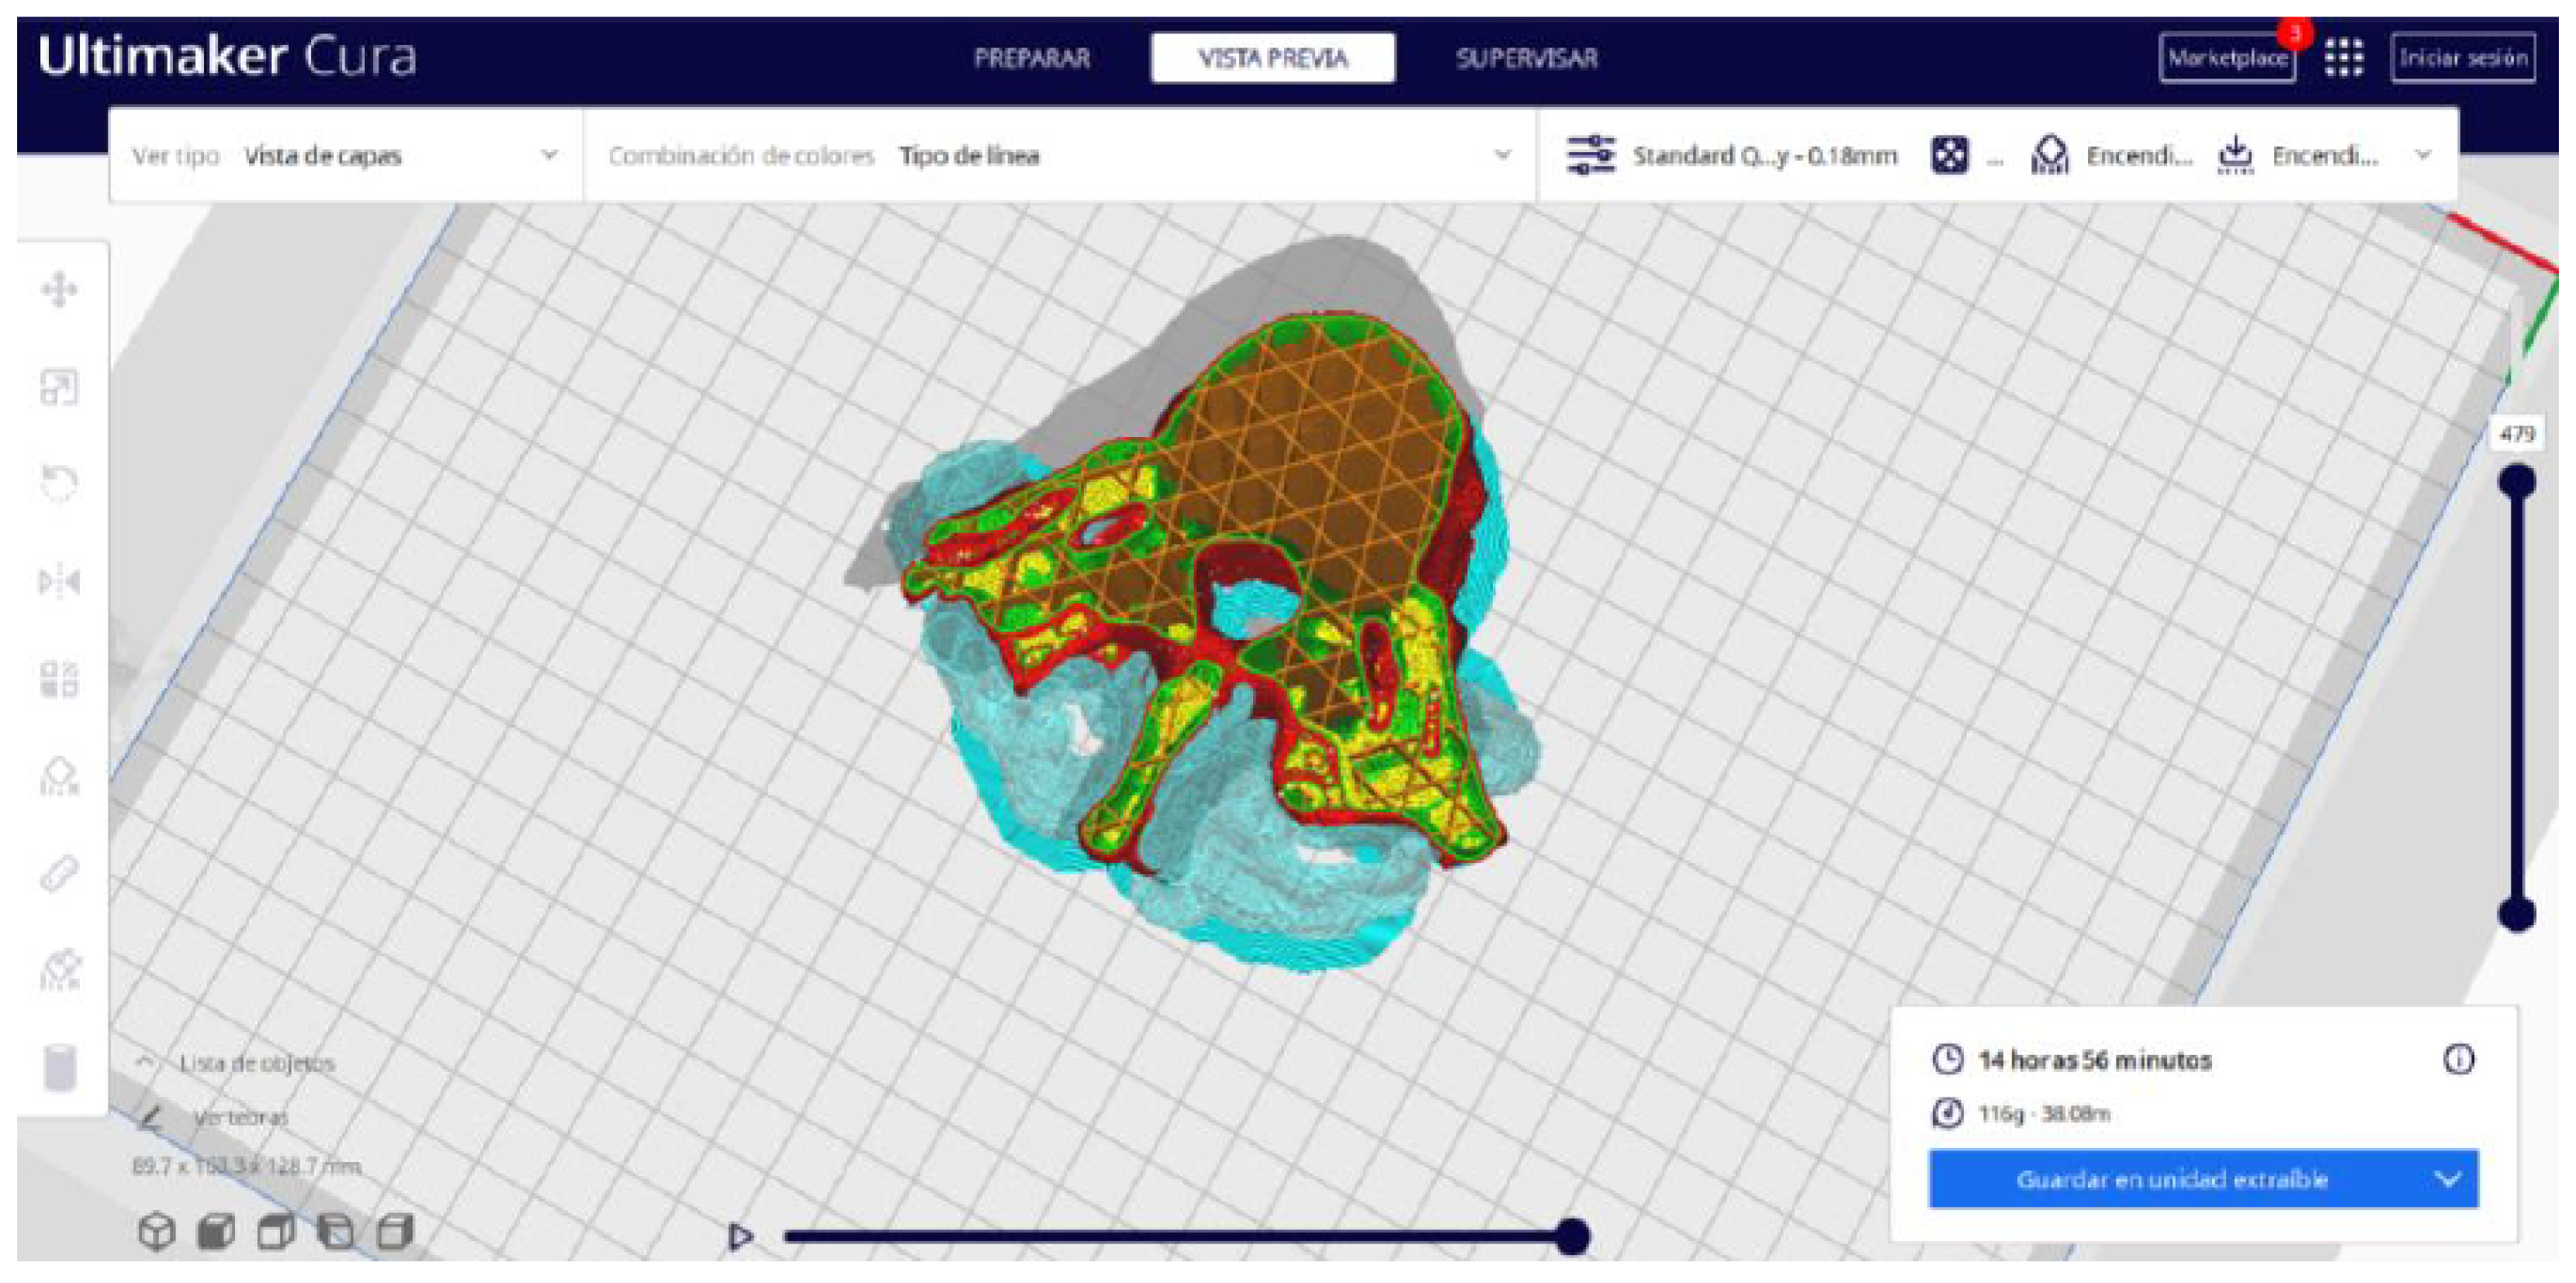

2.2. STL-to-GCODE File Conversion

- In order to continue the STL file to GCODE conversion process, select the “Segmentation” option in Ultimaker Cura.

- The segmentation tool provides valuable information such as the estimated model weight and estimated printing time, among other crucial data.

- Once the segmentation is complete, go to the “Preview” option. Here, a sidebar will appear on the right side of the screen, giving you the ability to preview the materialisation process layer by layer, from the base to the top of the model.

3.1.2. STL-to-GCODE File